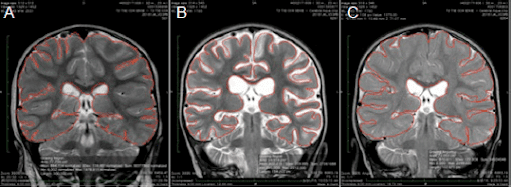

The second child is a two year old girl who was the first child in Dr. Harch’s second group of over 60 drowned children, nearly all of whom were treated within 6 months of drowning from 5/2016 to present. Her case was published in Medical Gas Research in 2017 (https://www.medgasres.com/temp/MedGasRes72144-6908434_191124.pdf). Her MRI scans below show a global loss of brain tissue one month after her drowning and a near complete regrowth and restitution of brain volume after normobaric oxygen by nasal cannula and hyperbaric oxygen. At the time of initiation of the nasal cannula oxygen she was a thrashing semi-conscious little girl. At the time of the final MRI she was walking and talking (see the videos in the link above).

The MRI slices below are what are called coronal slices, a view from the top of the head to the bottom. In each slice you are looking directly at this little girl. The left side of the image is the right side of her head. MRI scan A is 3 days after drowning. MRI scan B is 31 days after drowning where there has been a 12.3% loss of brain tissue, seen as increased white color on the scan (white is the cerebrospinal fluid or water of the brain). MRI scan C is 27 days after her 40th HBOT or 162 days after drowning. This is normally the time when one sees near-maximal loss of brain tissue. Instead, she has experienced a 13.9% increase in brain tissue.